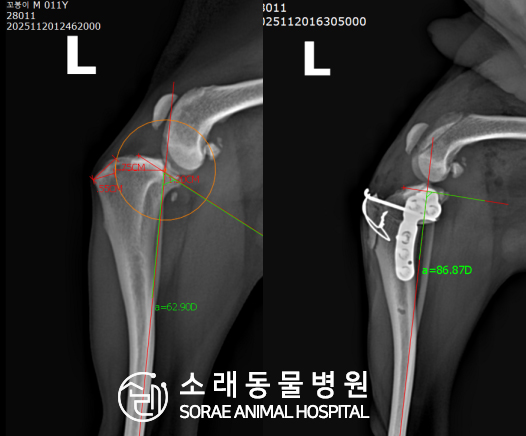

십자인대파열 수술 사례 - #288 꼬봉이

계산식으로 사전에 계획해두었던 플랜에 따라 경골을 절제하고

플레이트와 스크류를 사용하여 임플란트를 적용해 주었습니다.

반대 방향으로 밀려나 어긋나있던 대퇴골과 정강이가

제 자리를 찾으면서 무릎의 각도가 교정된 것을 확인할 수 있습니다